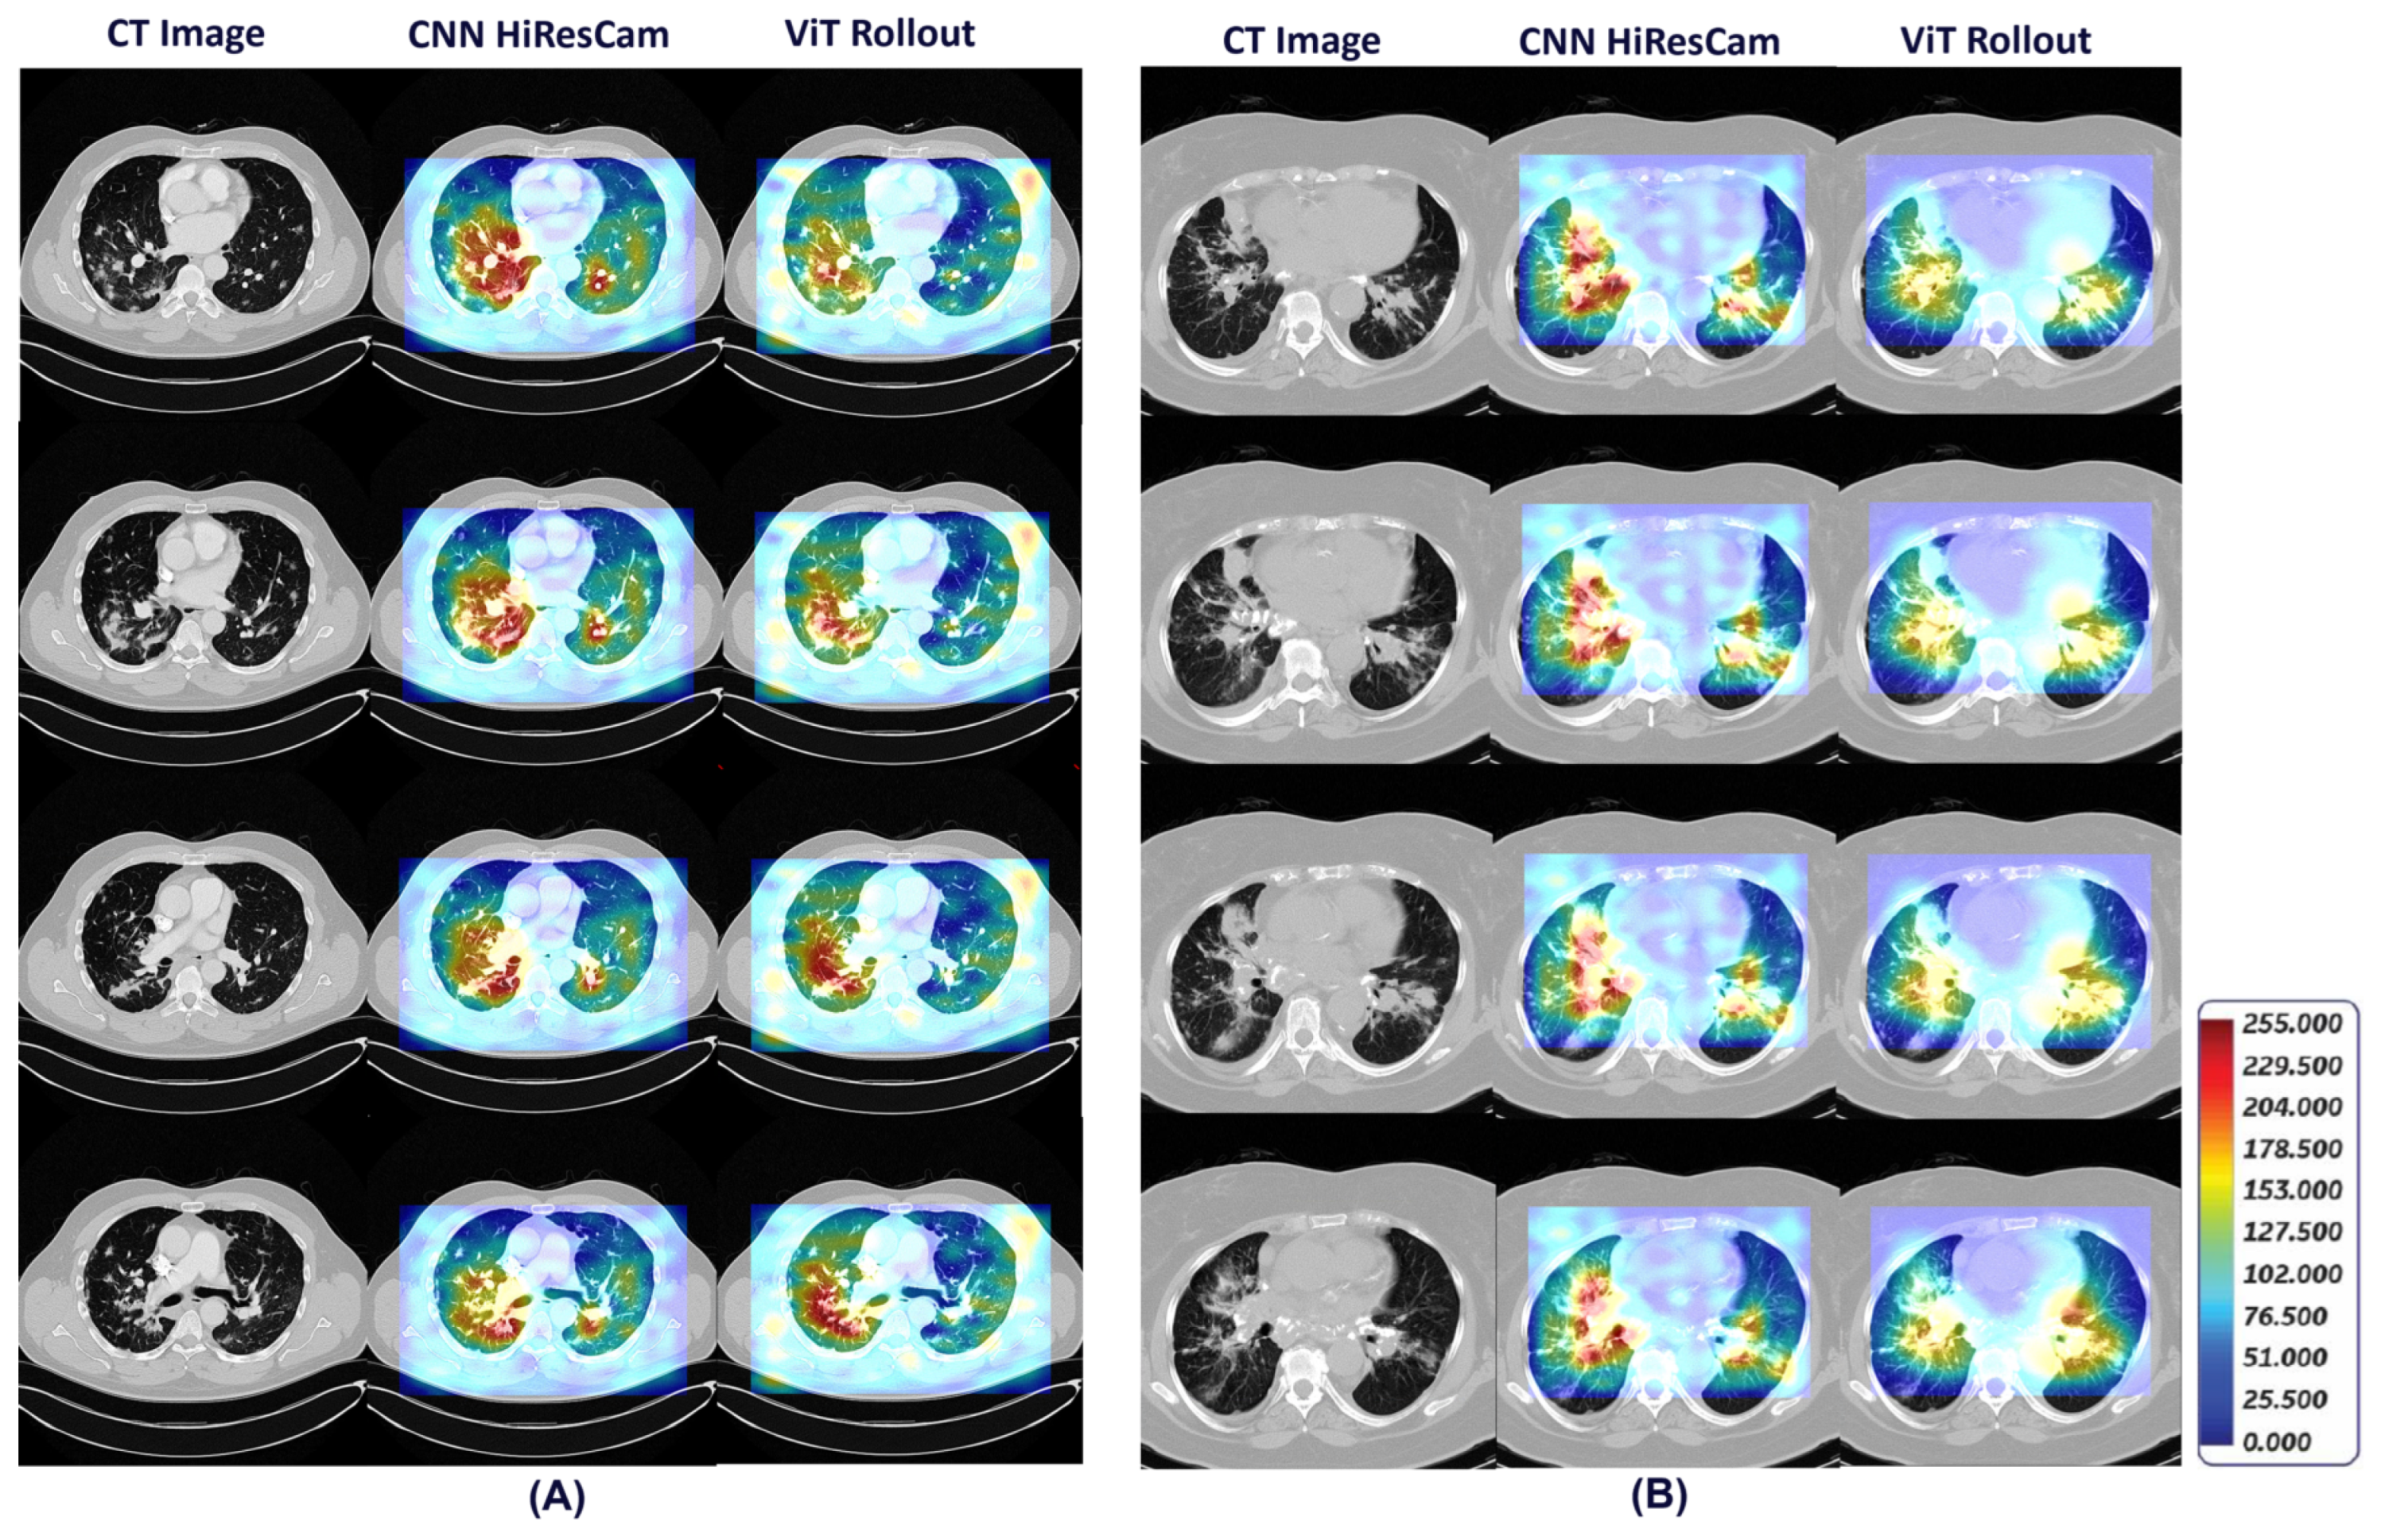

- Our framework also provides visual explainability for classification of pulmonary sarcoidosis vs lung malignancies (LCa), that suggests regions of interest that are considered important by the network for making the prediction.

2.3. Generating Visual Explanations for Predictions

- Draelos, R.L.; Carin, L. Hirescam: Faithful location representation in visual attention for explainable 3d medical image classification. arXiv:2011.08891, arXiv:2011.08891 2020.

- Abnar, S.; Zuidema, W. Quantifying attention flow in transformers. arXiv:2005.00928, arXiv:2005.00928 2020.